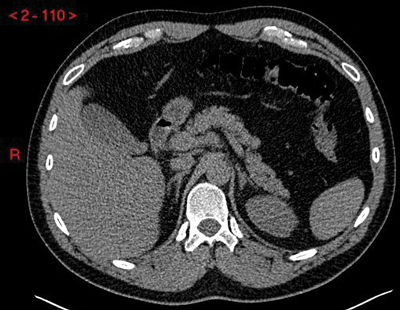

Adrenal glands are seen on CT in the shape of an inverted ‘V’ or ‘Y’ with a body and a medial and lateral limb (Figure 1). Each limb is smooth in outline and should be uniform in thickness, measuring 5-7mm, and the adrenal should measure up to 3cm in length.

Figure 1: Unenhanced CT demonstrating normal anatomical position and inverted ‘Y’ shape of the adrenal glands.